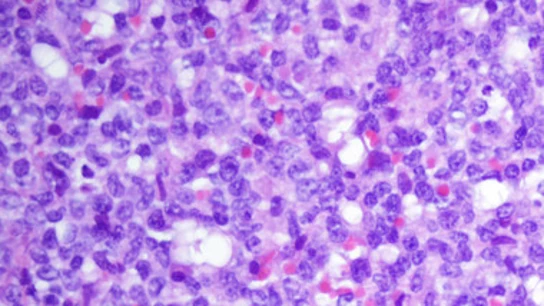

Investigadores del Institut d'Investigacions Biomèdiques August Pi i Sunyer (Idibaps) de Barcelona han descifrado por primera vez el epigenoma completo del tipo de leucemia más frecuente, la leucemia linfática crónica, y han abierto la puerta al desarrollo de nuevas terapias al proporcionar un mapa en alta resolución de sus funciones.

El estudio, publicado en la revista 'Nature Medicine', ha identificado más de 500 nuevas alteraciones en la función del genoma que son específicas de esta leucemia, y comparándola con el mapa de las células sanas, ha revelado las regiones que cambian su funcionalidad, "dianas potenciales para nuevas terapias".